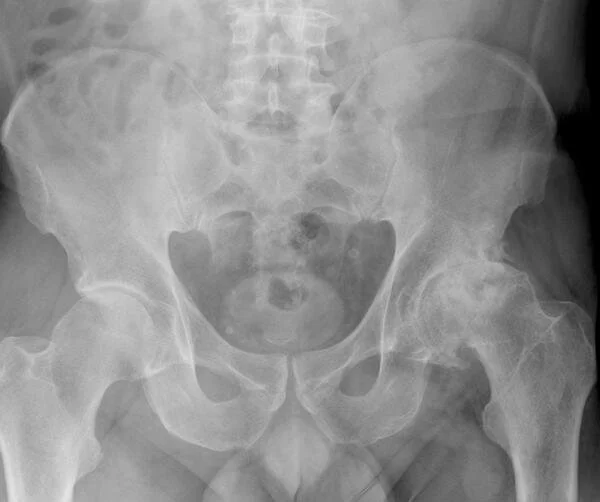

Клинично артрозата се проявява със ставна болка при натоварване, сутрешна скованост, постепенно ограничаване на движенията и в по-напреднали стадии – деформации. Най-често са засегнати коленете и тазобедрените стави.

Болката в тазобедрената става често започва постепенно и в началото може да бъде интерпретирана като временен проблем. Важно е обаче пациентът да разбере как се развива ставното износване и кога симптомите започват да показват реална структурна промяна в ставата. Ако искате да разберете как протича целият процес — от първите оплаквания до възможностите за съвременно лечение и операция — можете да прочетете пълното ръководство за смяна на тазобедрена става тук:

👉 https://www.dryordanov.com/publikacii-d-r-yordanov/rukovodstvo-protezirane-tbs